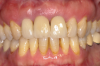

Fig 3. Placement of an implant in a young adult. A female patient had had a congenitally missing maxillary lateral incisor restored when she was 20 years old. Ten years later (Fig 2) the implant-supported restoration was in an infraocclusion state, shorter than the neighboring teeth, due to continuous skeletal growth. Radiograph (Fig 3) showed the marginal bone level of the implant was not affected.

Figure 3

Numerous clinical studies of skeletal changes and alveolar bone growth modifications around single implant-supported restorations in the esthetic zone in growing pigs and human case reports have been published.24-27 This issue has attracted particular attention in young individuals, most of whom required implant therapy due to congenital agenesis or trauma. A topic of thorough discussion among clinicians has been whether to use dental implants in young patients at all to replace missing teeth and, if so, what is the optimal age to place them with regard to possible skeletal changes that might follow. Implants become ankylosed to the bone in an identical way that an avulsed tooth behaves following late re-implantation.28 Such ankylosed teeth as well as dental implants do not adapt to eruptive processes of the surrounding skeletal growth and thus develop infraocclusion, which can severely affect esthetic appearance by the tooth or restoration being shorter than the neighboring teeth, which continue their growth (Figure 2 and Figure 3). Additionally, interproximal contact opening has been observed between the ankylosed crown and nearby natural crowns. Several in vivo experiments that examined osseointegrated implants in young populations concluded that dental implants should not be placed in young patients until their permanent dentition is fully erupted and their skeletal growth completed.29 Such recommendation was even more accentuated when the esthetic zone was involved.